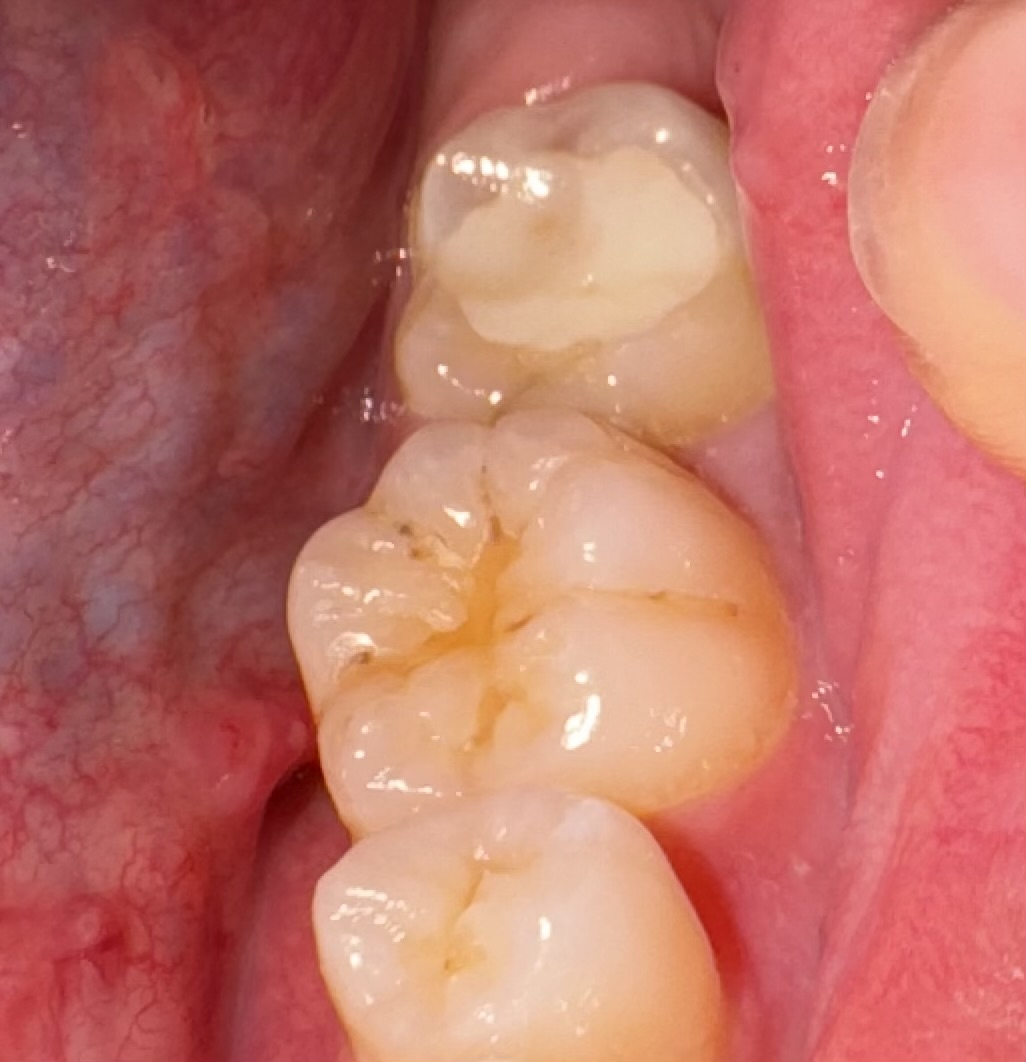

左下6番の溝の部分に黒い部分ができたり、穴っぽいものができた気がします。

また、左下6番〜7番付近で甘いものを食べると染みたり痛くなっちゃいます。たまに何にもしなくてもズキッとすることもあります。

左下6番が原因の痛みなのか、それとも神経を抜いた左下7番が原因なのか教えて頂きたいです。よろしくお願いします。

甘いものでしみるということですから、神経を抜いていない6番に虫歯がある可能性も高いと思います。7番の近心にレジンで修復がされておるのではないか?と思いますが、どうでしょうか?フロスの習慣がなければ6番の遠心も隣接面虫歯になっているということはよくあると思います。

6番の咬合面、頰面溝にCR修復されているように見えますから奥歯の磨き方が下手な方なのかも?と想像しています。

写真を拝見いたしましたが見える範囲では大きなむし歯はありません。

仰るような黒い点は極々初期のむし歯かもしれませんし単なる着色かもしれません、ここは歯医者さんで診てもらった方がいいと思います。

6番ではそのような痛みは出そうにないので7番を疑います、この歯は抜髄したようなので痛みの原因は一連の抜髄根管充填の不備が考えられます。